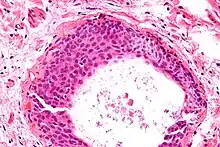

Histologically, there are nests of transitional epithelial (urothelial) cells with longitudinal nuclear grooves (coffee bean nuclei) lying in abundant fibrous stroma.

- Micrograph of a Walthard cell nest, the entity Brenner tumours are thought to arise from. H&E stain.